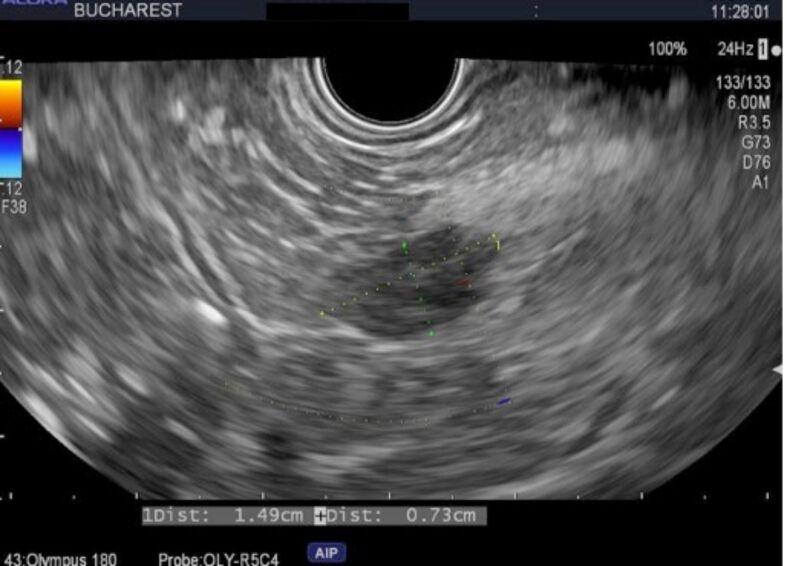

PATIENTS, MATERIALS AND METHODS: This is a single-center, retrospective case series including all patients with functional (F) and non-functional (NF) pNETs treated with EUS-RFA in the Department of Gastroenterology, Emergency Clinical Hospital of Bucharest, Romania, between March 2023 and March 2024 and followed for a mean period of 11.6 months. Technical success, clinical, sonographic and radiological response, adverse events (AEs) rate and severity were assessed.

A total of five out of nine EUS-RFA were performed for pNETs, with a majority of NF-pNETs. In this pNET group, the mean size of the lesions was 13 mm. Technical success was achieved in 100% of patients and persistent clinical remission of hypoglycemia in the insulinoma case was attained. In the NF-pNET subgroup, two patients were successfully radiologically treated with complete disappearance of the lesions, one lesion showed cystic transformation, and one had modest size reduction at follow-up imagery. One procedure-related early AE occurred: mild abdominal pain with quick resolution. No major complications, nor death were reported.

患者、材料与方法:这是一项单中心回顾性病例系列研究,纳入了2023年3月至2024年3月期间在罗马尼亚布加勒斯特急诊临床医院胃肠病科接受EUS-RFA治疗的所有功能性(F)和非功能性(NF)pNETs患者,并进行了平均11.6个月的随访。评估了技术成功率、临床、超声和放射学反应、不良事件(AE)发生率及严重程度。

9例EUS-RFA治疗中共有5例用于pNETs,其中大多数为NF-pNETs。在这个pNETs组中,病变的平均大小为13毫米。100%的患者实现了技术成功,胰岛素瘤病例实现了低血糖的持续临床缓解。在NF-pNETs亚组中,2例患者经放射学成功治疗,病变完全消失,1个病变出现囊性变,1个在随访影像中大小略有缩小。发生了1例与手术相关的早期AE:轻度腹痛且很快缓解。未报告重大并发症和死亡情况。